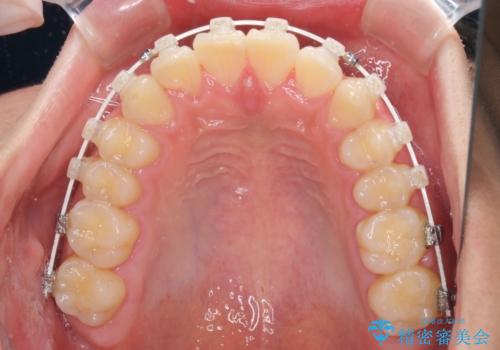

深い咬み合わせとデコボコ ワイヤー矯正で短期治療

- 審美装置

マウスピース矯正の自己管理が面倒とのことで、ワイヤー矯正により治療を行うこととしました。

インビザラインでの治療も可能でしたが、深い咬み合わせと奥歯の咬み合わせを改善するにあたり、ワイヤー矯正の方が治療期間を短縮できると判断し、ワイヤー矯正をお勧めしました。